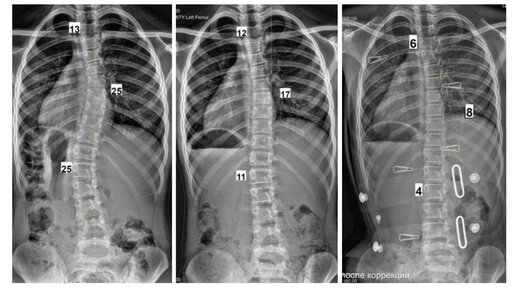

История сегодняшней пациентки – пример того, как занятия спортом могут успешно сочетаться с лечением сколиоза. А еще доказательство того, что было бы желание, а время заниматься ЛФК всегда найдется!

Итак, девочке 8 лет. Она занимается художественной гимнастикой. Тренировки 3-4 раза в неделю по 3 часа...